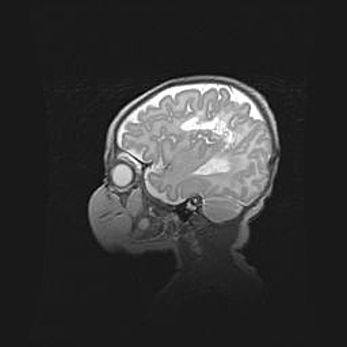

Мальформация Денди-Уокера. Киста задней черепной ямки.

Агенезия мозолистого тела.

Возраст: 2,5 месяца

Вес: 2420 г

Пол: женский

Окружность головы: 37 см

Срок гестации: 32 недели

Мальформация Денди—Уокера — редкий вид патологии ЦНС, представляющий собой врожденный порок развития каудального отдела ствола и червя мозжечка, ведущий к неполному раскрытию срединной (Мажанди) и латеральных (Лушка) апертур IV желудочка мозга. Для этогно синдрома характерна триада симптомов: гипотрофия червя мозжечка и/или полушарий мозжечка, кисты задней черепной ямки, гидроцефалия различной степени. В 70% случаев порок сочетается и с другими аномалиями головного мозга, в частности с агенезией мозолистого тела.